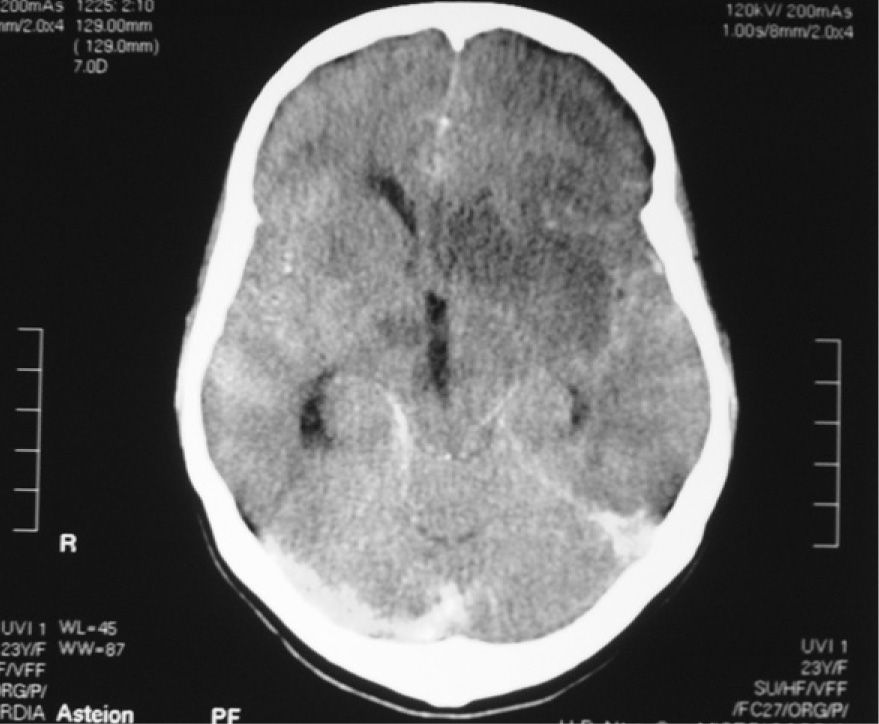

Meningitis

Es una enfermedad infecciosa que ataca las meninges del cerebro y la médula espinal.

Esta, es producida mas comúnmente por bacterias como el neumococo, meningococo, hemofilo y listeria que llegan al cerebro por el torrente sanguíneo o a través de alguna infección en el oído o senos paranasales. También puede contagiarse de manera viral o fungica.

La meningitis es una enfermedad de cuidado, ya que se presenta como una simple gripe con síntomas comunes, pero puede ser potencialmente mortal. También puede dejar secuelas en aquellos que la superan, como: perdida de la audición, perdida de la memoria, impedimentos en el aprendizaje, daño cerebral y psicomotor, convulsiones, insuficiencia renal, entre otros.